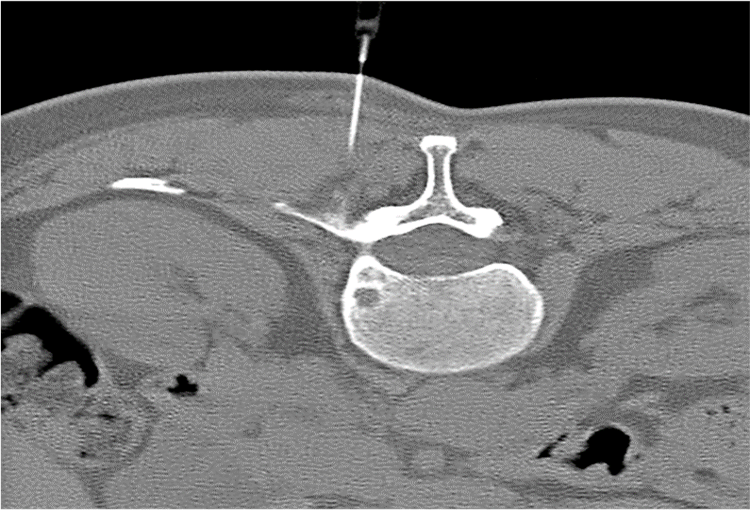

120 kV / 20 mAs / 1 mm

Before FBP (Noise 189) VS After ClariCT.AI (Noise 46) 76% Denoising